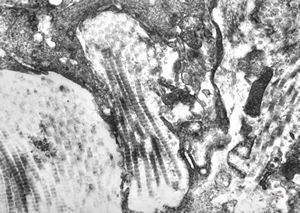

M, 43y. | myeloid leukemia … Auer bodies

M, 43y. | myeloid leukemia … Auer bodies

M, 43y. | myeloid leukemia … Auer bodies